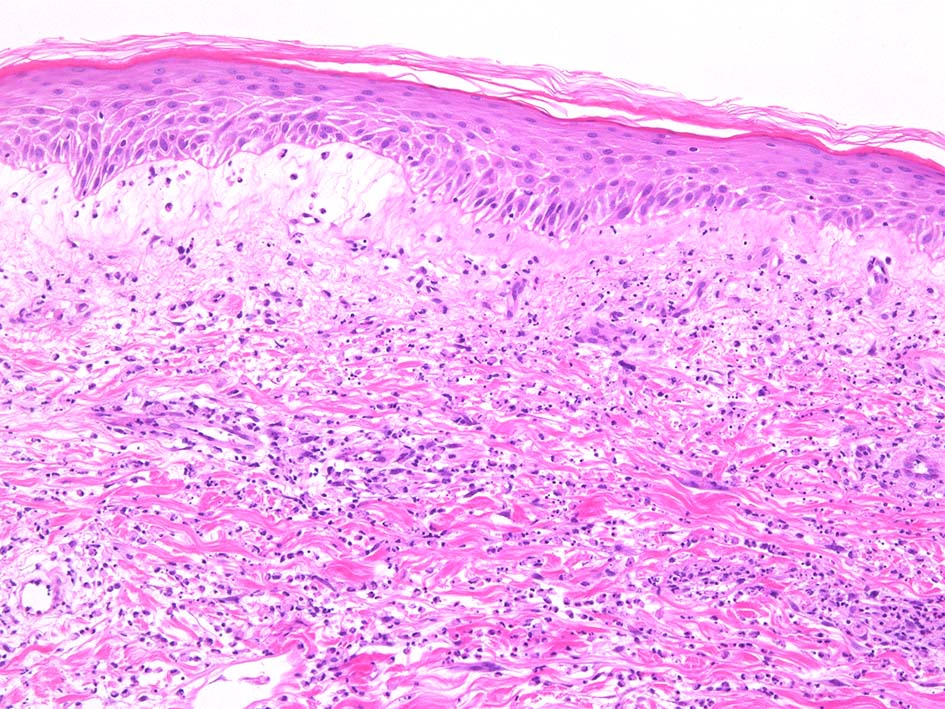

Case01 前腕皮膚腫瘤

46 year old female

咳痰などの上気道炎症状発症後4日で口内炎が出現. 37.3℃の微熱, 関節痛あり. 5日めに手, 膝に水疱を伴う発赤が出現. 倦怠感持続. 10日後左眼が腫れ受診する.

lt

HE x40. Sweet病最盛期皮膚病変の所見があります.

表皮下水疱, 真皮上層の細血管周囲に密な好中球浸潤あり.(thumb nail clickで大きなphotoが見られます)